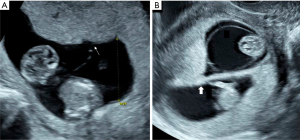

Monozygotic twins are classically considered the result of division of a single embryo and account for approximately 30% of all twin pairs worldwide (1,2). The timing of the split is related to the observed number of placentas and amniotic sacs, with earlier division leading to more complete separation (Figure 1) (1,3). Chorionicity refers to the number of placentas in the pregnancy. This can be determined in the first trimester by ultrasound identification of a single placental mass with a thin dividing membrane that inserts directly into the placental surface (T-sign) and absence of placental tissue extending in between the intertwin membrane (λ-sign) with a sensitivity and specificity of up to 98–100% (Figure 2) (4-7). Correct identification of monochorionicity is critical because it defines the risk profile and the range of complications that can occur. The mortality for monochorionic twins is twice that of dichorionic twins and four times that of singleton pregnancies with a highest rate of previable pregnancy loss prior to viability most commonly attributable to the unique features of the monochorionic placenta (8,9).

The initial diagnosis of TTTS is made by ultrasound identification of both polyhydramnios for the recipient twin by a maximum vertical pocket (MVP) of amniotic fluid of >8 cm and oligohydramnios for the donor twin with a MVP <2 cm, which is well above the 95th percentile and below the 5th percentile across gestational age (31). Measurement of the MVP should be performed with the patient in the dorsal supine position and in an area free of fetal parts or the umbilical cord in order to avoid underestimation of the amniotic fluid volume. Due to oligohydramnios, the donor twin may appear “stuck” to the placenta or uterine wall. On occasion the fetus may appear suspended from the uterine wall, termed the “chandelier sign” from being wrapped in the membrane and the folded membrane may appear thicker from being folded on itself. Use of the Quintero staging criteria is widely accepted as the standard to communicate the severity of disease (32). It includes assessment of bladder filling, Doppler assessment of the umbilical artery, ductus venosus and umbilical vein, presence of hydrops or fetal demise (Table 1). Importantly, each component of the classification system is a categorical assessment. For instance, to meet criteria for critically abnormal Dopplers absent or reversed end diastolic velocity in the umbilical artery or ductus venosus a-wave is required. Increased resistance or abnormal indices are not sufficient to satisfy criteria for TTTS Stage 3 or higher but may provide important insight into the overall clinical assessment.